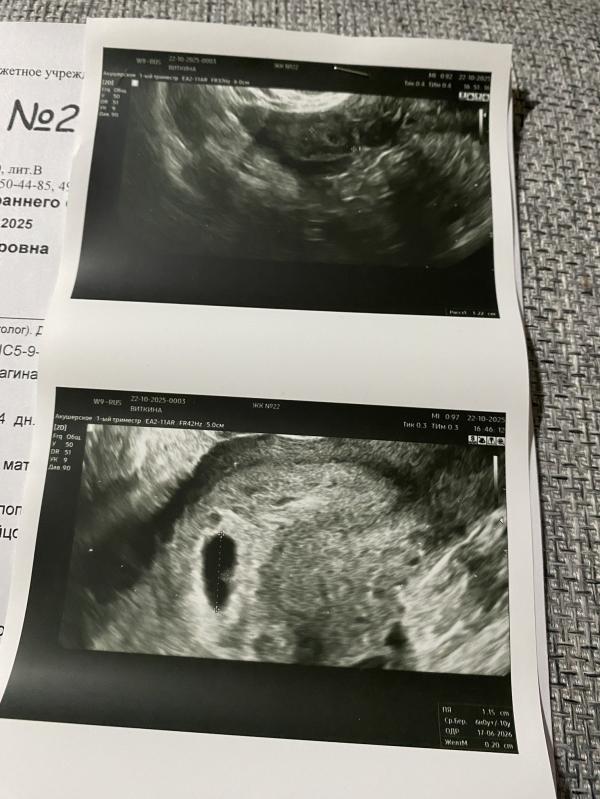

СВД 11.5мм

ЖМ 2мм

Подскажите, что её могло смутить? Размеры СВД и ЖМ? Она уже должна была там увидеть эмбрион?

По месячным срок около 6 недель.

Потом начала водить дальше, видимо, увидела размеры ПЯ и ЖМ, что-то её смутило. Долго водила, разглядывала. В итоге, поставила маточную беременность и сказала приходить через неделю. «Возможно, эмбриончик появится».